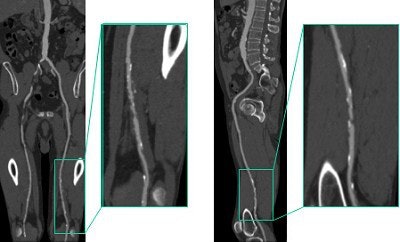

The capability of 16-slice CTA to rescan rapidly enables a second exam to better visualize extremity arterial occlusions, he reported. Improved tibial artery visualization provides very useful presurgical information for potential graft planning.

"The arteries of lower extremity inflow and runoff can be reliably depicted with minimal venous enhancement using multislice CT angiography," Sebben added. In the elderly, vessel tortuosity can be better appreciated, which also facilitates presurgical evaluation, he said. An added bonus of CTA is that it can detect incidental findings in organs.

Clinical cases illustrate the advantages of 16-slice vs. 4-slice and 8-slice imaging. Evaluation using 16-slice imaging enabled vessel visualization over a distance of 1,800 mm, compared with 1,500 mm for 4-slice scanners. This was particularly relevant in the case of a tall man with coexisting carotid and iliac arterial disease. Images courtesy of Dr. Ruben Sebben.